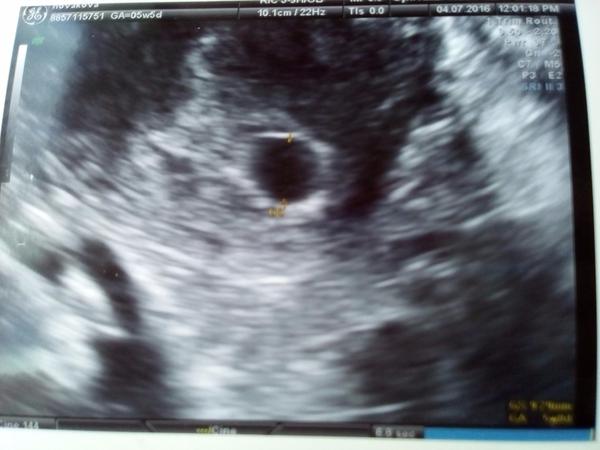

ahojky, tak já byla na UTZ minulé pondělí, dle MS jsem byla v 5.tt, doktor teda říkal,že to vypadá na 4.tt a je to taky taková malá tečka, foto přikládám: